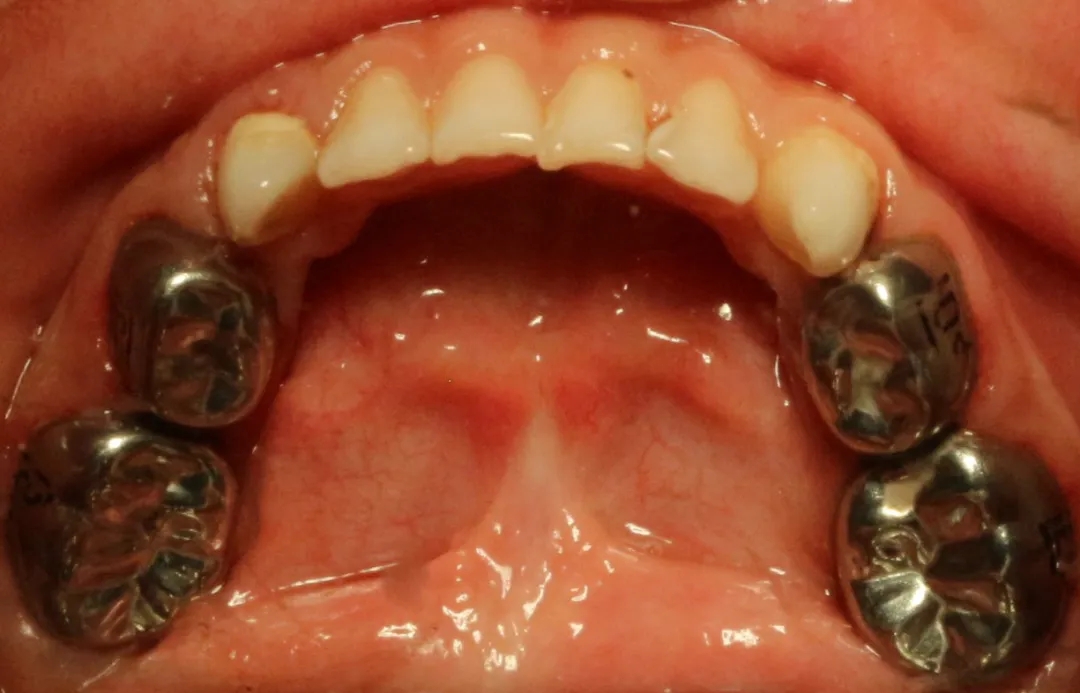

▲儿科乳牙金属预成冠【什么是乳牙金属预成冠】

儿童乳牙金属预成冠是一个预先成型的,与牙齿非常贴合的不锈钢金属牙冠,套在乳牙上可以保护牙齿并加强牙齿的强度,能够确保乳牙非常健康的被恒牙替换。

用金属冠恢复乳磨牙的外形和咀嚼功能,恢复患牙正常咬合关系,防止充填物的脱落,继发龋的产生和牙体组织的折裂,因此能有效保护缺损较大的乳磨牙至替牙期,从而保证继承恒牙顺利萌出,减少恒牙列错和颌畸形的发病,并促进后期颌面部的正常发育。